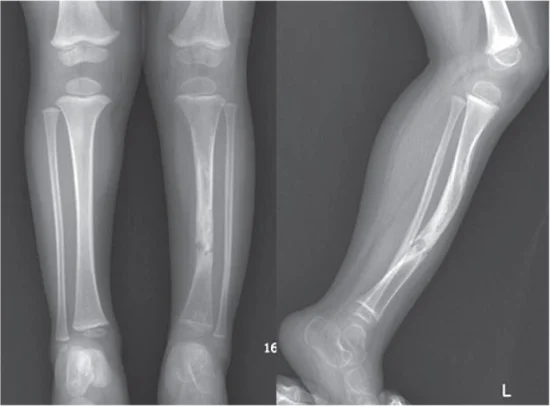

- Рентгенография костей: Наиболее информативный метод для выявления костных изменений. Рентгенограммы обычно выполняются на запястьях (области лучезапястных суставов) и/или коленных суставах. На снимках видны характерные признаки рахита: расширение метафизов, нечеткость контуров эпифизов, снижение плотности костной ткани.

- Со стороны конечностей: утолщения в области запястий ("рахитические браслеты") и голеностопных суставов, искривление длинных трубчатых костей, чаще всего ног. В зависимости от типа деформации, ноги могут приобретать О-образную (гену варум) или Х-образную (гену вальгум) форму.

| О-образные ноги (гену варум) | Нижние конечности | Колени развернуты наружу, голени искривлены, ноги напоминают букву "О" при сомкнутых стопах. |

| Х-образные ноги (гену вальгум) | Нижние конечности | Колени соприкасаются или сближены, а лодыжки разведены, ноги напоминают букву "Х". |